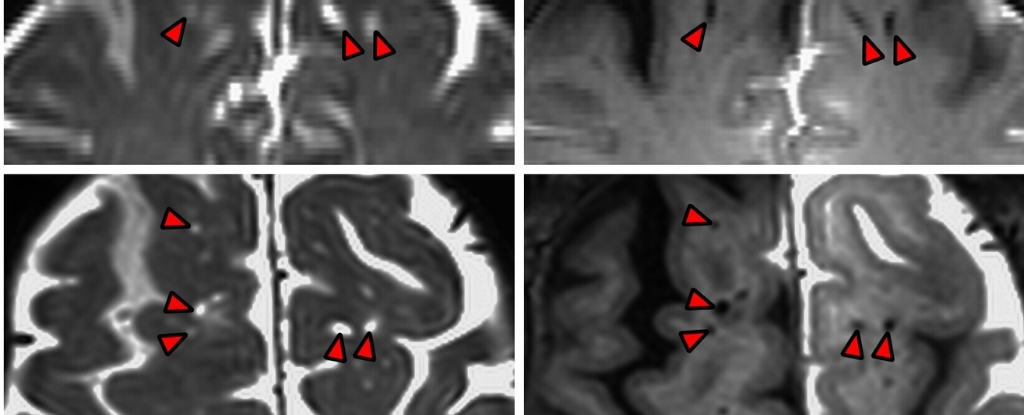

پیانتینو و همکارانش در OHSU اولین کسانی هستند که توانستهاند مایع بیرنگ مغزی را در حال جریان به درون بافت مغز انسان زنده مشاهده کنند. این پژوهش با رضایت پنج بیمار که تحت جراحی مغز قرار داشتند و نیاز به تخلیه مایع مغزی-نخاعی داشتند، ممکن شد. دانشمندان قبل از جایگزینی این مایع، آن را با مادهای تیره ردیابی کردند و سپس با استفاده از تصویربرداری رزونانس مغناطیسی (MRI) محل جریان مایع را در مغز بیماران نقشهبرداری کردند.

نتایج نشان داد که مغز انسان بهصورت تصادفی این مایع را جذب نمیکند، بلکه مایع از طریق مسیرهای خاصی که در امتداد عروق خونی قرار دارند، به اعماق بافتهای عصبی نفوذ میکند. این فضاهای پیرامونعروقی با سلولهای مغزی احاطه شدهاند که یک مانع نیمهنفوذپذیر ایجاد میکنند.

ارین یاماموتو، جراح مغز و اعصاب OHSU، گفت: در تصاویر MRI میتوان مشاهده کرد که این فضاهای پیرامونعروقی به تدریج روشنتر میشوند، همانطور که ماده ردیاب تیره به اعماق مغز نفوذ میکند.

این مطالعه که در مجله PNAS منتشر شده، نشان میدهد که فضاهای مملو از CSF در مغز انسان ساختارهای ثابت و بدون تغییر نیستند، بلکه بهعنوان مجراهای فعال عمل میکنند و مایع مغزی-نخاعی را به سراسر مغز توزیع میکنند.